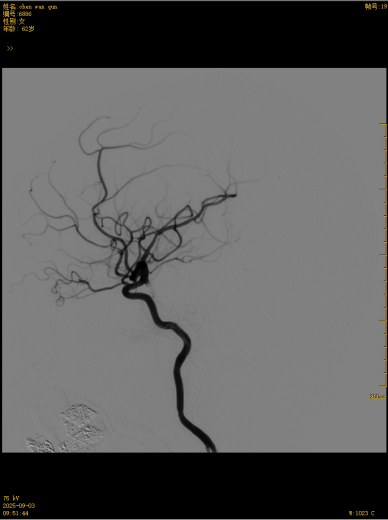

颅内动脉瘤并非肿瘤,而是脑血管壁薄弱处鼓起的“血泡”,如同轮胎鼓包般随时可能破裂出血,致残致死率极高。传统治疗或需开颅夹闭,创伤大且恢复慢;以往普通支架辅助栓塞对宽颈、巨大、夹层等复杂动脉瘤效果有限,复发率高。此次应用的最新血流导向密网支架,作为中国首款远端闭合结构的国产高端器械,彻底颠覆传统治疗逻辑——以“血流重塑”为核心,通过高金属覆盖率构建“人工血管壁”,将动脉瘤与正常血流物理隔离,诱导血管内皮细胞爬覆形成新生血管,实现动脉瘤解剖学治愈,1年完全闭塞率超80%,远超传统技术。

这款国产创新技术的优势不止于疗效:通体显影设计让支架定位精准到毫米级;超弹性材质与优化编织工艺实现极致贴壁,兼顾支撑力与柔顺性,适配复杂迂曲脑血管;操作更轻巧、创伤更小,仅需大腿根部米粒大小切口即可完成手术,可实现患者术后可快速康复。本次手术中,团队在DSA引导下精准释放支架,全程耗时短、出血少,术后造影显示,动脉瘤内血流即刻变得迟缓,载瘤动脉通畅,重要分支血管保护完好。患者术后恢复良好,未出现任何神经功能障碍,术后不久即快速康复出院,重获健康,恢复正常生活工作。